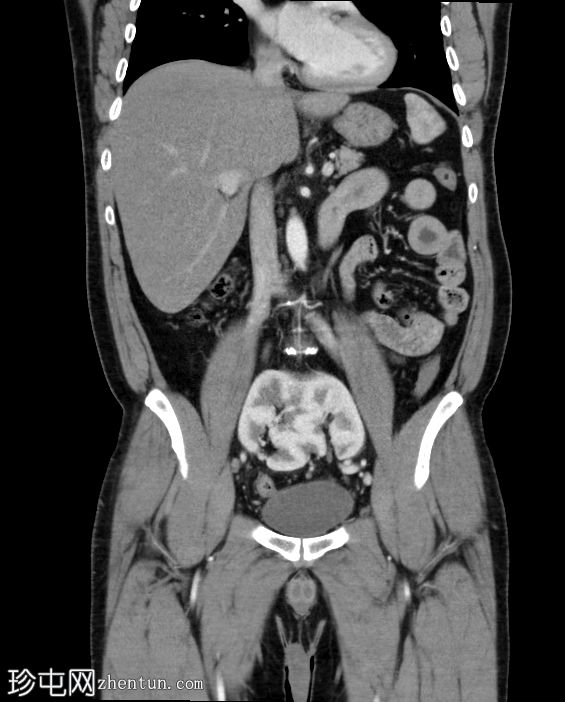

冠状位

平扫

轴位增强扫描(门静脉期)

冠状位增强扫描(门静脉期)

双肾上极和下极融合,形成扁平肾,在轴位、冠状位和三维图像上均可见。

有两条独立的输尿管,左右输尿管分别独立引流至膀胱。

未见结石或反流压力改变。

本病例展示了扁平肾,这是一种解剖变异,其特征是双肾上极和下极完全融合。这与马蹄肾不同,马蹄肾仅下极通过峡部连接。

虽然扁平肾可能是一种偶然发现,但评估是否存在相关并发症(如肾结石和反复

泌尿

道感染)非常重要。